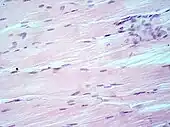

H&E is the combination of two histological stains: hematoxylin and eosin. The hematoxylin stains cell nuclei a purplish blue, and eosin stains the extracellular matrix and cytoplasm pink, with other structures taking on different shades, hues, and combinations of these colors.[5][6] Hence a pathologist can easily differentiate between the nuclear and cytoplasmic parts of a cell, and additionally, the overall patterns of coloration from the stain show the general layout and distribution of cells and provides a general overview of a tissue sample's structure.[7] Thus, pattern recognition, both by expert humans themselves and by software that aids those experts (in digital pathology), provides histologic information.

Hematoxylin principally colors the nuclei of cells blue or dark-purple,[6][15][14] along with a few other tissues, such as keratohyalin granules and calcified material. Eosin stains the cytoplasm and some other structures including extracellular matrix such as collagen[5][7][14] in up to five shades of pink.[8] The eosinophilic (substances that are stained by eosin)[5] structures are generally composed of intracellular or extracellular proteins. The Lewy bodies and Mallory bodies are examples of eosinophilic structures. Most of the cytoplasm is eosinophilic and is rendered pink.[10][15] Red blood cells are stained intensely red.

Muscle tissue, cell nuclei (blue-purple), cell body (pink).